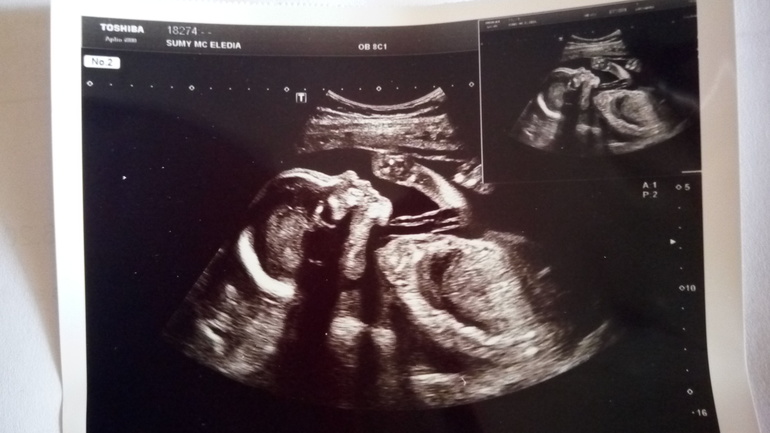

Узи 24 нед. Все хорошо

Какая же она классная!!!! Смотрела бы на неё постоянно. Кажется, что в этот раз доця будет похожа на папу)) Толкает я во всю. Наверное думает, что мама резиновая)) Решила в этот раз сделать фото малышки)